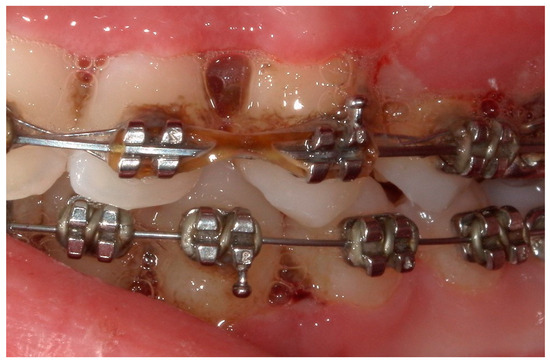

4.1. Case 1